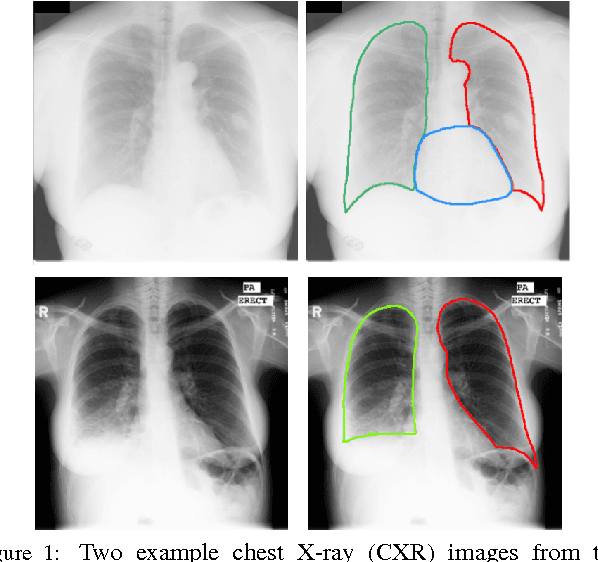

Chest X-ray (CXR) is one of the most commonly prescribed medical imaging procedures, often with over 2-10x more scans than other imaging modalities such as MRI, CT scan, and PET scans. These voluminous CXR scans place significant workloads on radiologists and medical practitioners. Organ segmentation is a crucial step to obtain effective computer-aided detection on CXR. In this work, we propose Structure Correcting Adversarial Network (SCAN) to segment lung fields and the heart in CXR images. SCAN incorporates a critic network to impose on the convolutional segmentation network the structural regularities emerging from human physiology. During training, the critic network learns to discriminate between the ground truth organ annotations from the masks synthesized by the segmentation network. Through this adversarial process the critic network learns the higher order structures and guides the segmentation model to achieve realistic segmentation outcomes. Extensive experiments show that our method produces highly accurate and natural segmentation. Using only very limited training data available, our model reaches human-level performance without relying on any existing trained model or dataset. Our method also generalizes well to CXR images from a different patient population and disease profiles, surpassing the current state-of-the-art.